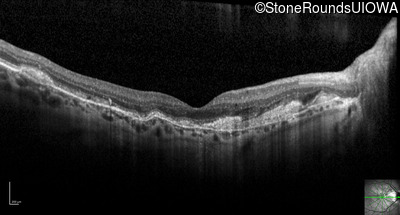

Optical Coherence Tomography - Left - 20/25 +3

Exemplar / OCT Stack